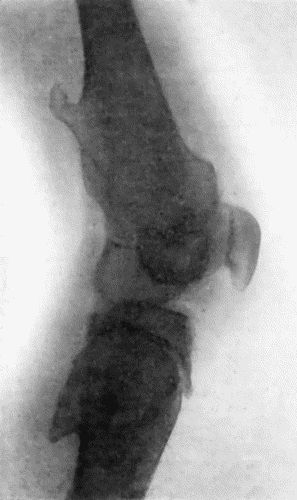

| 162. | Bones of Knee in Charcot's Disease | 533 |

| 163. | Charcot's Disease of Left Knee | 534 |